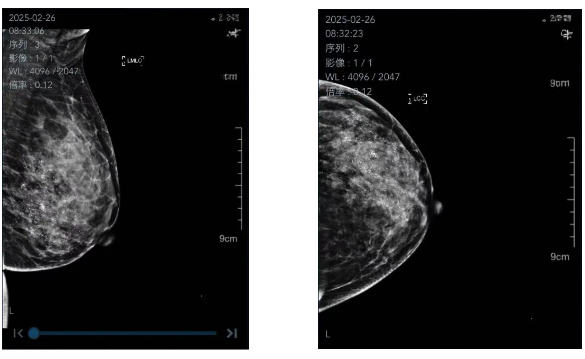

聽完醫(yī)生的介紹后,陶女士選擇在市人民醫(yī)院做乳腺鉬靶檢查。在檢查中,醫(yī)生發(fā)現(xiàn)她左乳有多個(gè)比芝麻還小的鈣化點(diǎn),“手根本摸不到,乳腺彩超也無法顯現(xiàn)鈣化灶,要不是鉬靶看得清楚,根本發(fā)現(xiàn)不了!”

乳腺鉬靶(全稱乳腺X線攝影檢查),是目前國際上廣泛認(rèn)可的乳腺癌篩查“金標(biāo)準(zhǔn)”之一。它采用低劑量X射線,通過特殊的設(shè)備對乳房進(jìn)行不同角度的夾壓拍攝,生成高清晰度的乳腺組織圖像。如同為乳房拍一張精細(xì)的“黑白照片”,醫(yī)生能從中發(fā)現(xiàn)微小的鈣化點(diǎn)、腫塊或結(jié)構(gòu)扭曲等乳腺癌的早期跡象,甚至在您尚未觸摸到任何異常之前!